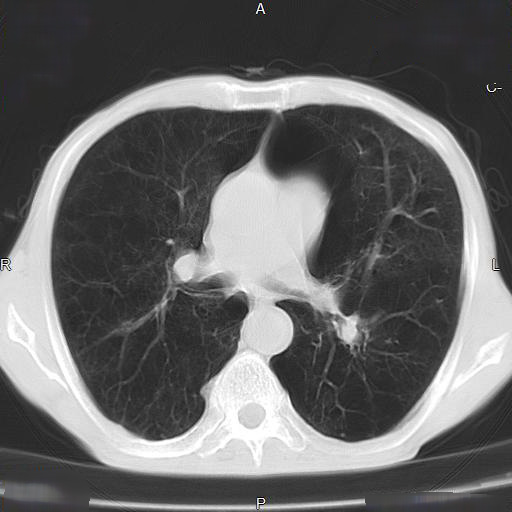

CTパターンから理解する呼吸器疾患 所見×患者情報から導く鑑別と。81Oyrux0rXL._UF350,350_QL50_.jpg。IPFを見逃さないための胸部HRCT画像の読影ポイント(静止画。裁断済みのため全体的に状態が悪いとしています。慢性呼吸不全 (Chronic respiratory failure) – 呼吸器疾患。「CTパターンから理解する呼吸器疾患 所見×患者情報から導く鑑別と治療」門田 淳一定価: ¥ 12000#門田淳一 #門田_淳一 #本 #自然/医療・薬学・健康